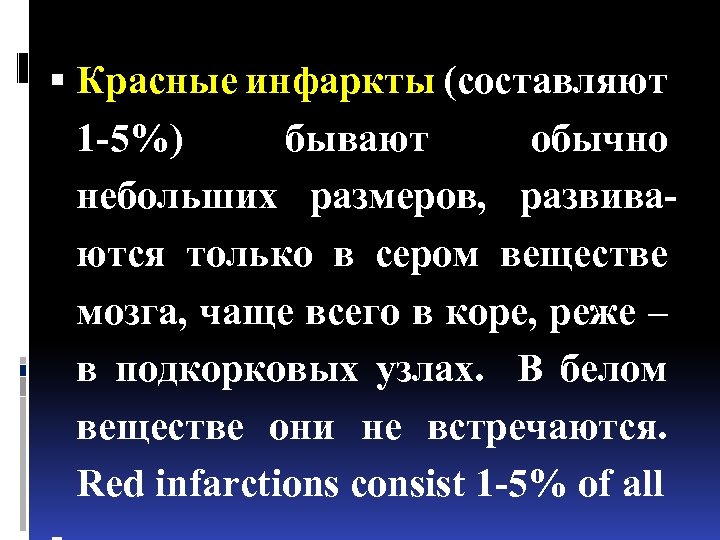

Красные инфаркты (составляют 1 -5%) бывают обычно небольших размеров, развиваются только в сером веществе мозга, чаще всего в коре, реже – в подкорковых узлах. В белом веществе они не встречаются. Red infarctions consist 1 -5% of all

Красные инфаркты (составляют 1 -5%) бывают обычно небольших размеров, развиваются только в сером веществе мозга, чаще всего в коре, реже – в подкорковых узлах. В белом веществе они не встречаются. Red infarctions consist 1 -5% of all

Развитию красного инфаркта всегда предшествует ишемия, затем присоединяется кровоизлияние в ишемизированную ткань.

Развитию красного инфаркта всегда предшествует ишемия, затем присоединяется кровоизлияние в ишемизированную ткань.